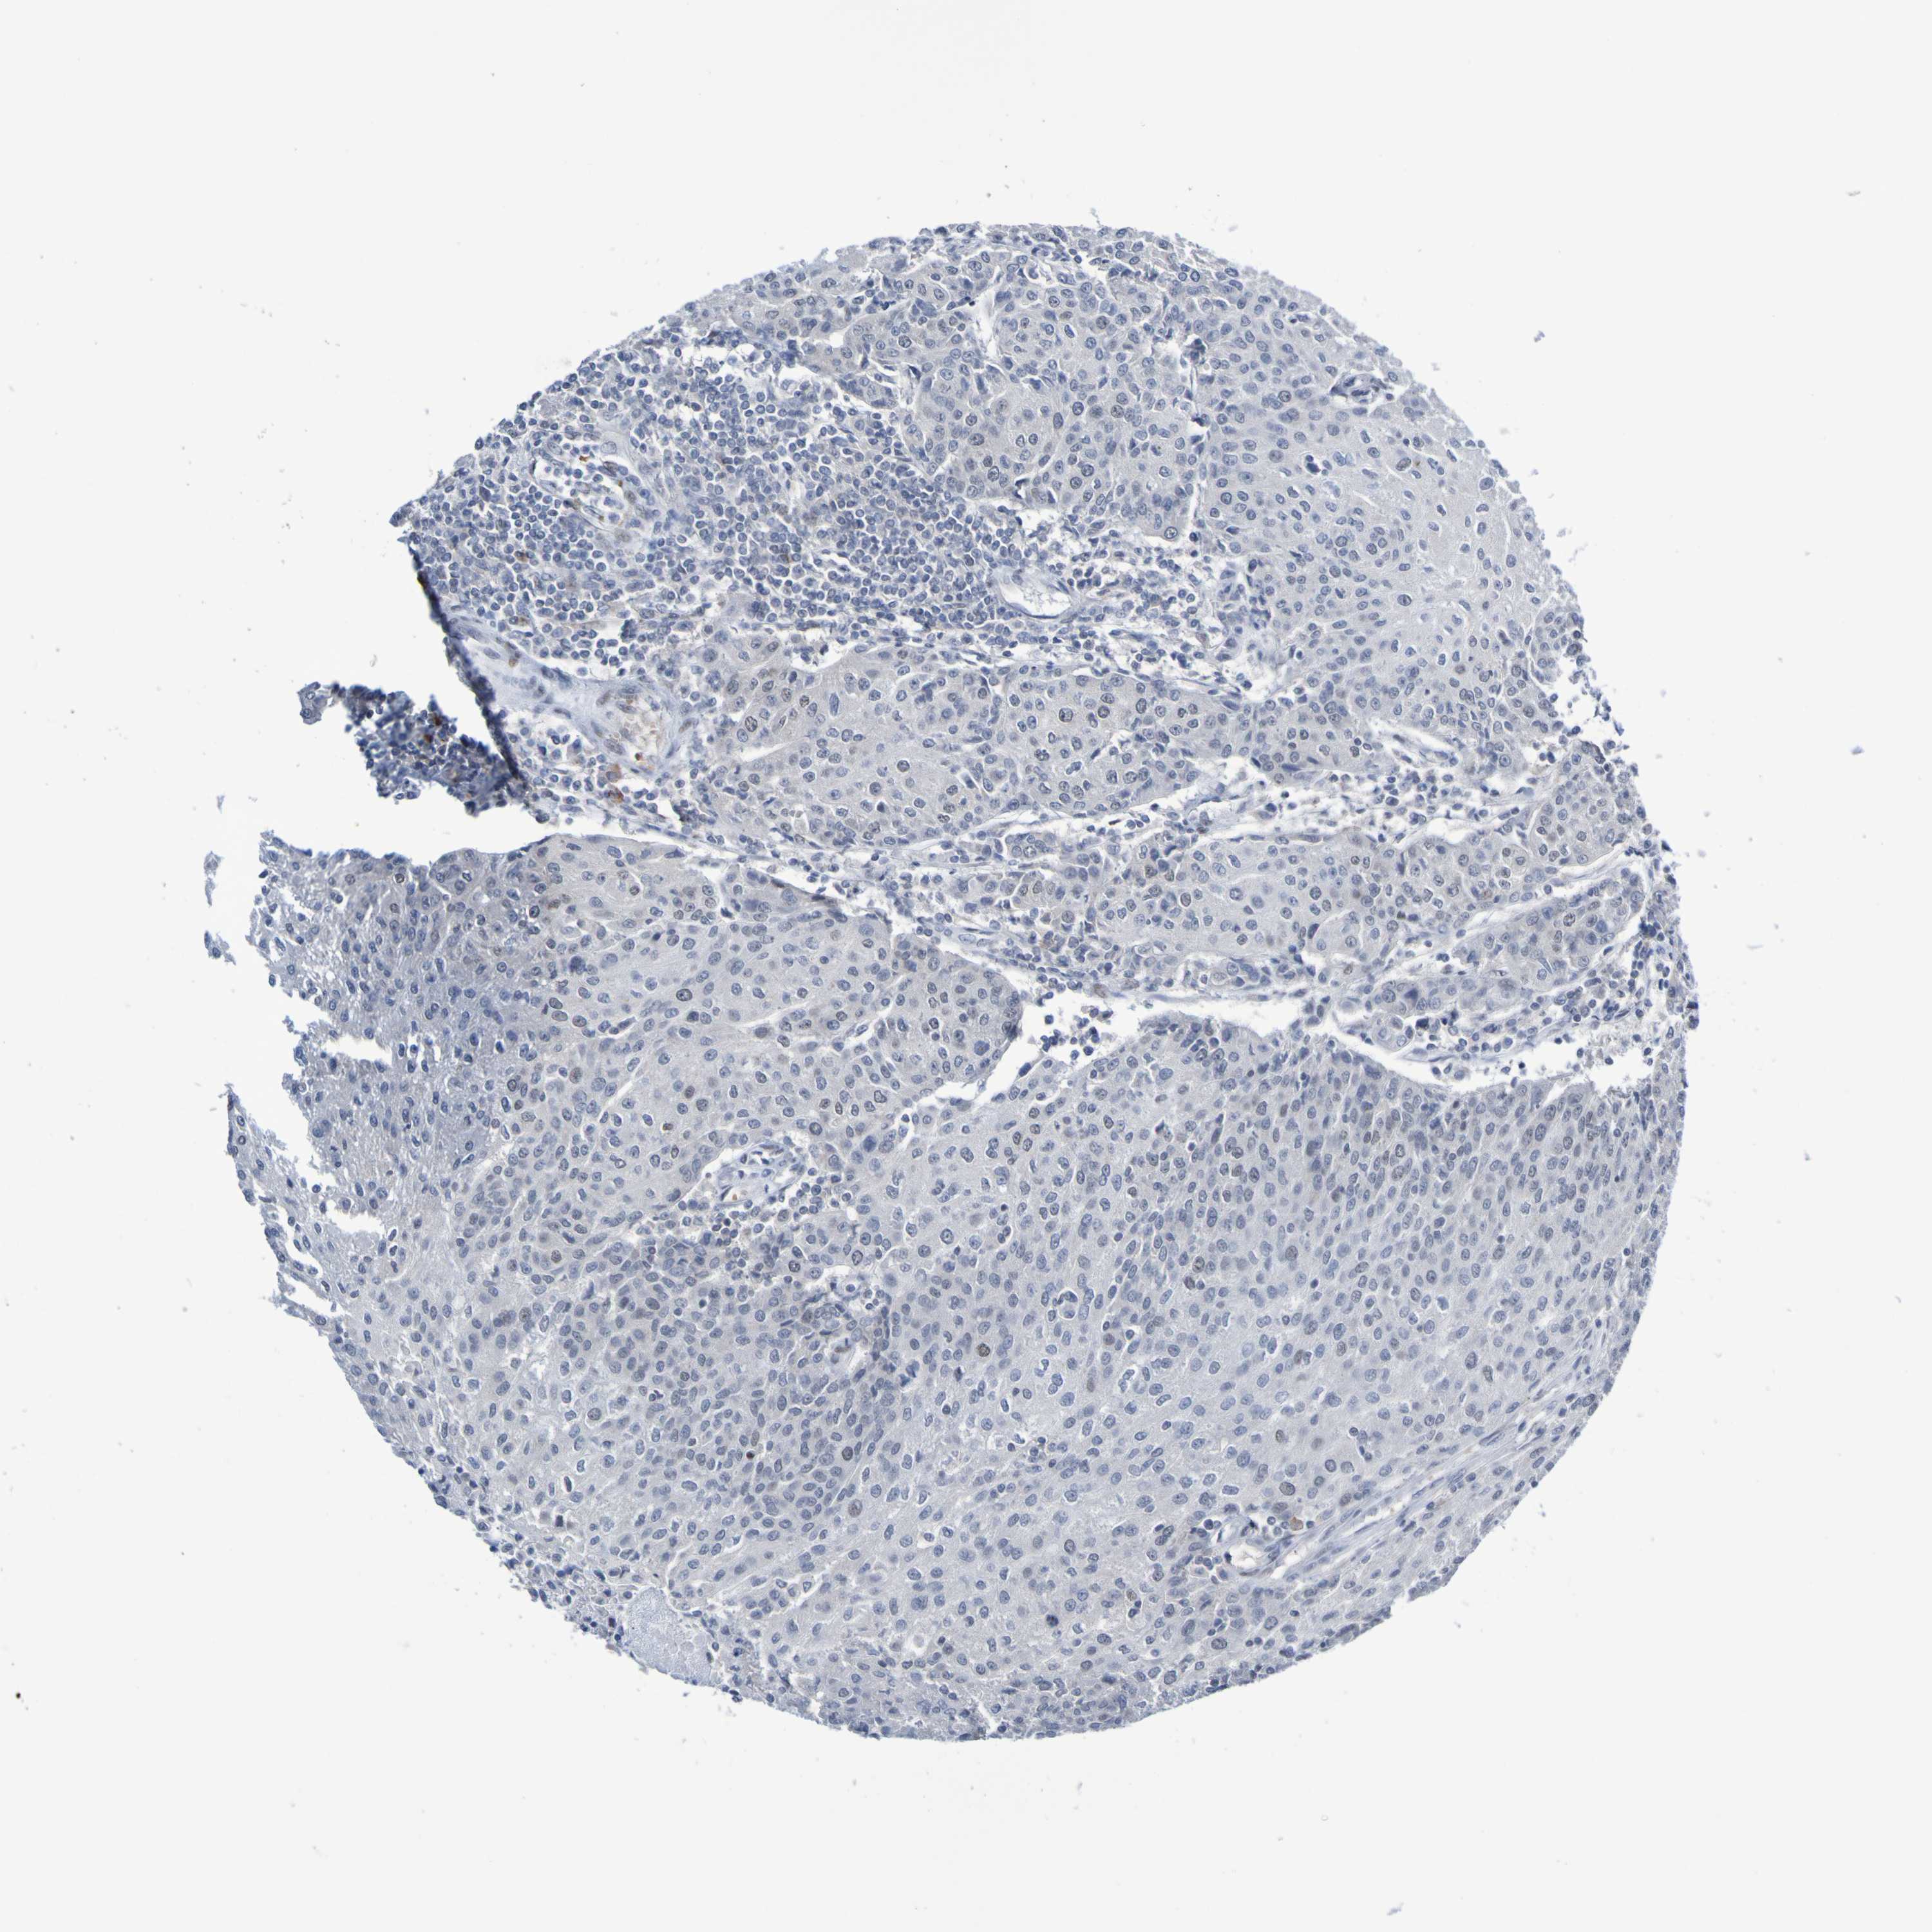

UROTHELIAL CANCER - Protein expressioni

A mouse-over function shows sample information and annotation data. Click on an image to view it in a full screen mode. Samples can be filtered based on level of antibody staining by selecting one or several of the following categories: high, medium, low and not detected. The assay and annotation is described here.

Note that samples used for immunohistochemistry by the Human Protein Atlas do not correspond to samples in the TCGA dataset.

Antibody stainingi

Antibody staining in the annotated cell types in the current human tissue is reported as not detected, low, medium, or high, based on conventional immunohistochemistry profiling in selected tissues. This score is based on the combination of the staining intensity and fraction of stained cells.

Each image is clickable and will lead to virtual microscopy that enables deeper exploration of all samples and also displays staining intensity scores, fraction scores and subcellular localization as well as patient and tissue information for each sample.

Antibody HPA011356

Staining

High

Medium

Low

Not detected

Intensity

Strong

Moderate

Weak

Negative

Quantity

>75%

75%-25%

<25%

None

Location

Nuclear

Cytoplasmic/membranous

Cytoplasmic/membranous,nuclear

Urothelial carcinoma, Low grade

Urothelial carcinoma, High grade